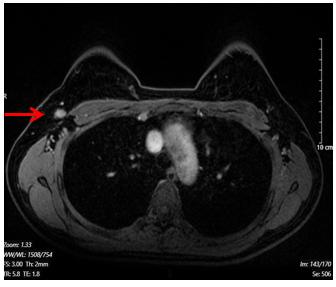

Hình 2. Hình ảnh chụp cộng hưởng từ tuyến vú. Hạch hố nách bên phải, có vỏ dày, kích thước 7x13mm (mũi tên màu đỏ)

· Hạch hố nách bên phải, chặng I có vài hạch, có vỏ dày, kích thước lớn nhất 7x13mm